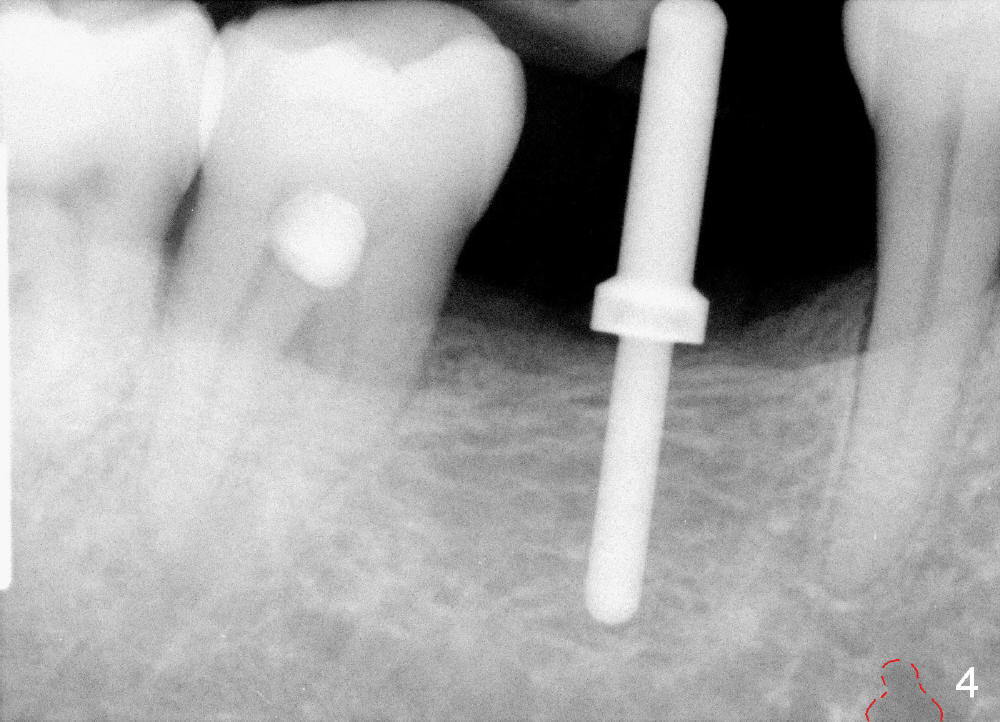

When a positioning pin is placed in the osteotomy with 10 mm deep, the sensor cannot be placed deep enough because of pin interference so no IAC is visible (Fig.4). When the pin is removed and the sensor is placed low enough, IAC is clearly shown, but the osteotomy is barely visible (Fig.5 pink dashed line). With information obtained from pre- (Fig.2,3) and intra- (Fig.4,5) op PA, twelve mm of osteotomy appears to be appropriate. A final implant (5.3x12 mm) is placed with separation from IAC (Fig.6, insertion torque 50 Ncm). A healing abutment is placed (Fig.7,8), which helps retain perio dressing (Fig.9). Two weeks later, the gingiva heals around the abutment (Fig.10). Four months postop, the implant appears to osteointegrate (Fig.11). A cemented abutment is placed (Fig.12). With supragingival margin, oral hygiene is easily maintained (Fig.13). Due to delayed placement, the gingival embrasure is extremely large (*). The issue is much less with immediate implant.